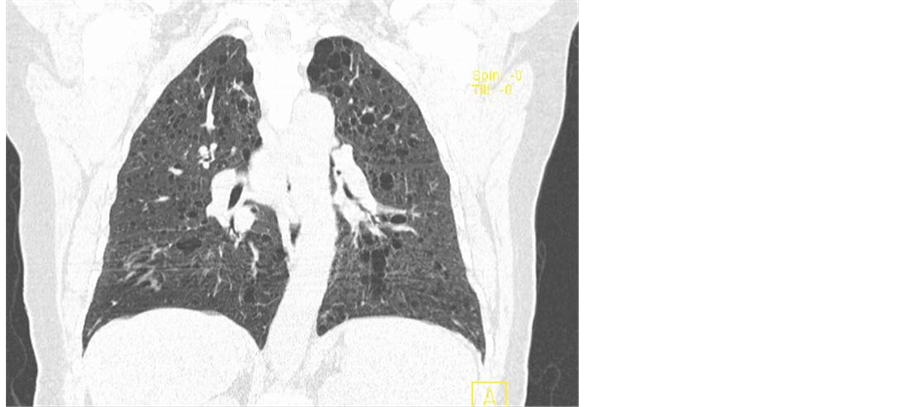

Despite becoming apyretic, shortness of breath, cough and hypoxaemia persisted and the patient was submitted to a pulmonary angiogram ct which revealed numerous thin-walled air cysts affecting upper and medial zones of both lungs (Figure 1), typical images of pulmonary lymphangioleiomyomatosis (Figure 2) [6] .

Figure 1. Multiple thin-walled round well-defined air-filled cysts throughout both lungs.